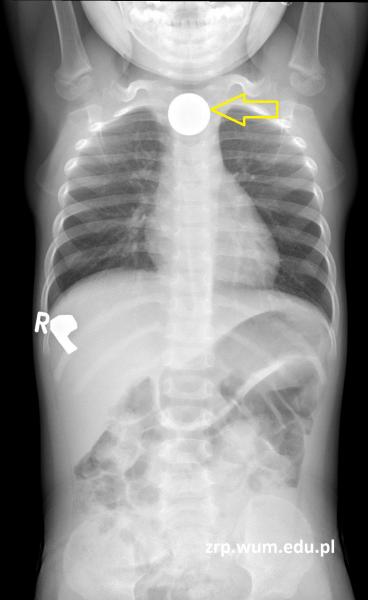

2-letnia dziewczynka z podejrzeniem połknięcia ciała obcego

Przypadek 57: 2-letnia dziewczynka z podejrzeniem ciała obcego w przewodzie pokarmowym - moneta 5 zł.

Rozpoznanie: Wykonano badanie RTG klatki piersiowej i jamy brzusznej - uwidoczniono okrągłe cieniujące ciało obce średnicy ok. 25 mm, rzutujące się na wysokości trzonów kręgów C7-Th2 (żółta strzałka).